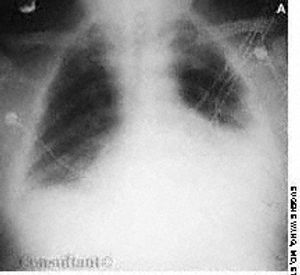

Over the previous 6 months, a 59-year-old man had experienced lethargy, fatigue, poor appetite, cold intolerance, and abdominal distention. His vital signs were normal; physical examination revealed periorbital and pretibial edema, distant heart sounds, and delayed reflexes.

Over the previous 6 months, a59-year-old man had experienced lethargy,fatigue, poor appetite, cold intolerance,and abdominal distention. Hisvital signs were normal; physical examinationrevealed periorbital andpretibial edema, distant heart sounds,and delayed reflexes.